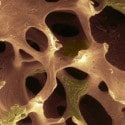

- 3. lépés. Kifejezve a porc, a csontszövet szklerotikus, ízületi felületek deformálódnak, lapított, marginális csont elszaporodását.

A csípőízület egy erős porc réteg (4 mm-es vastagság). Ezen túlmenően, ez a gazdagon vérrel. Ellenáll a nagy terhelés - a súlya a test, futás, ugrás, séta. Minden üt eloltották. A fejlesztés a kóros folyamatot, ami sok tényező:

Lebomlása ízületi porc kíséri a veszteség glikózaminoglikánokat. Ezért használat Antepartan (1 chondroprotector generációs Rumalonnal tartozik ugyanahhoz a csoporthoz), így megszakítja a porc és javítja a teljesítmény. Kombinált hondroprotektory utolsó generációs (Teraflex, Artron összetett képlet-C) ma már széles körben használják ízületi gyulladás.